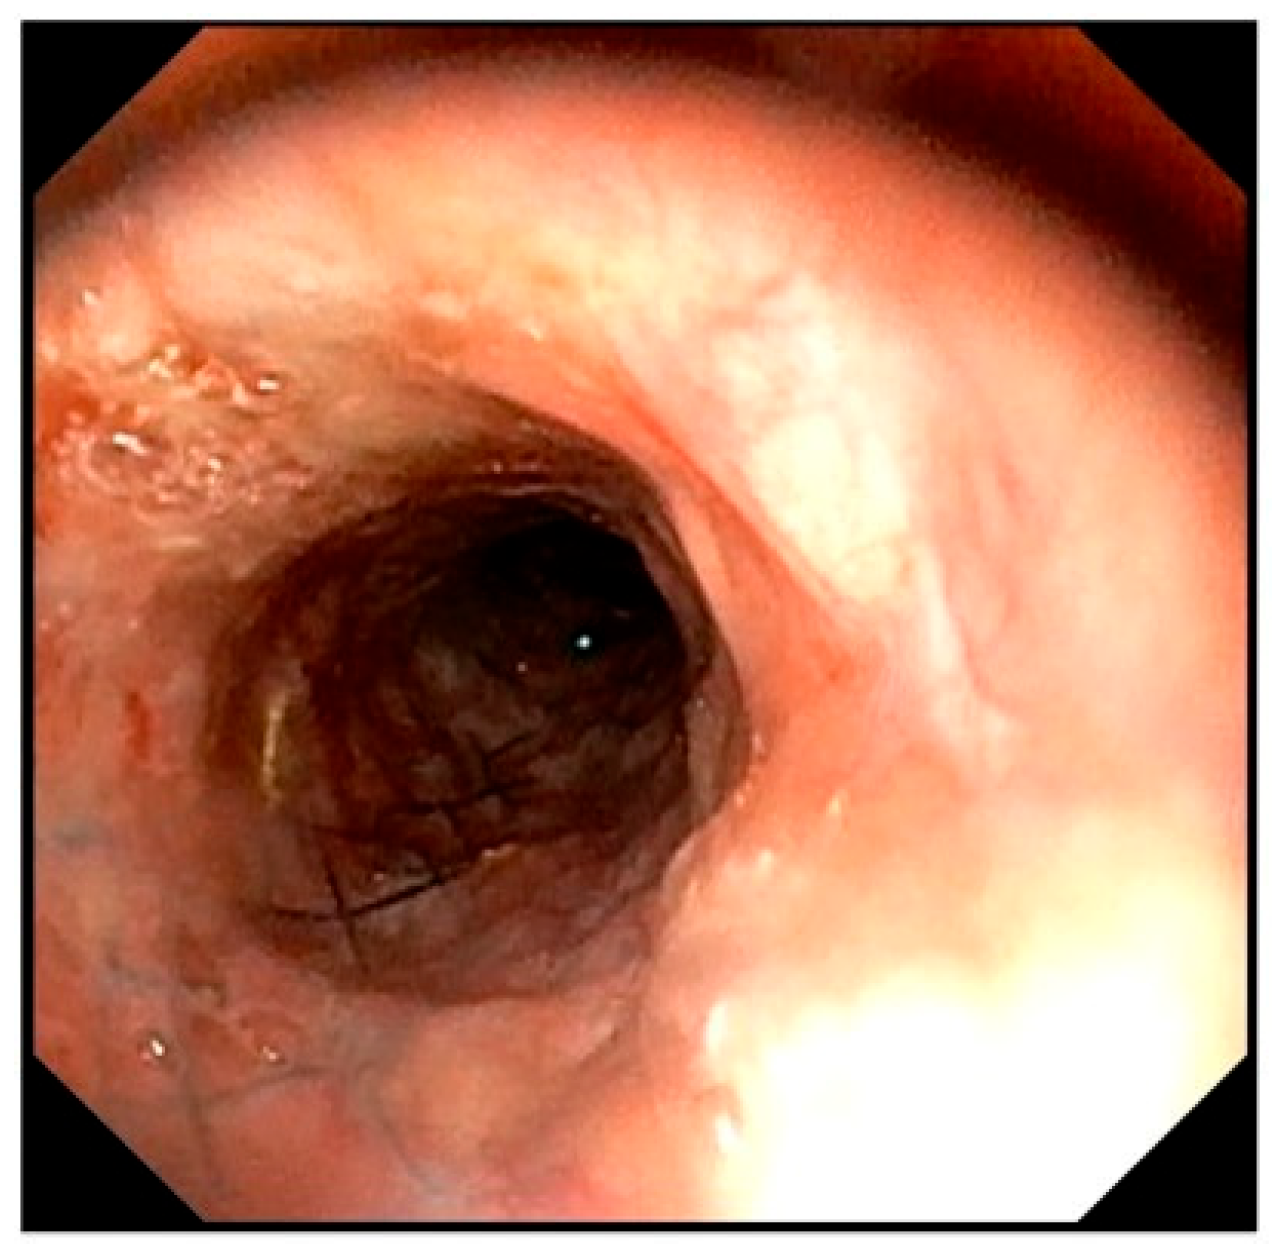

Figure 7. Bronchoscopic image obtained during unilateral arytenoid cartilage lateralization. The tracheal lumen maintains a circular shape.

As a treatment option, unilateral arytenoid cartilage lateralization was recommended and performed with the owner’s consent, with concurrent bronchoscopy performed at the time of surgery (Figure 7) Postoperatively, the respiratory status was temporarily stable, but the patient developed aspiration pneumonia on the second postoperative day and died.

To assess the durability of this external tracheal support over time, bronchoscopic findings obtained during subsequent unilateral arytenoid cartilage lateralization were reviewed. Despite persistent negative intraluminal pressure associated with laryngeal paralysis for five months, the tracheal lumen remained well maintained in a circular configuration. No progression of collapse at the cranial end of the stent or additional structural failure was observed. To date, no studies have evaluated the relative utility of ring-type prostheses versus PLLP for external reinforcement following stent failure. The present findings suggest that PLLP can serve as an effective complementary structure for stabilizing and reshaping a damaged tracheal stent.